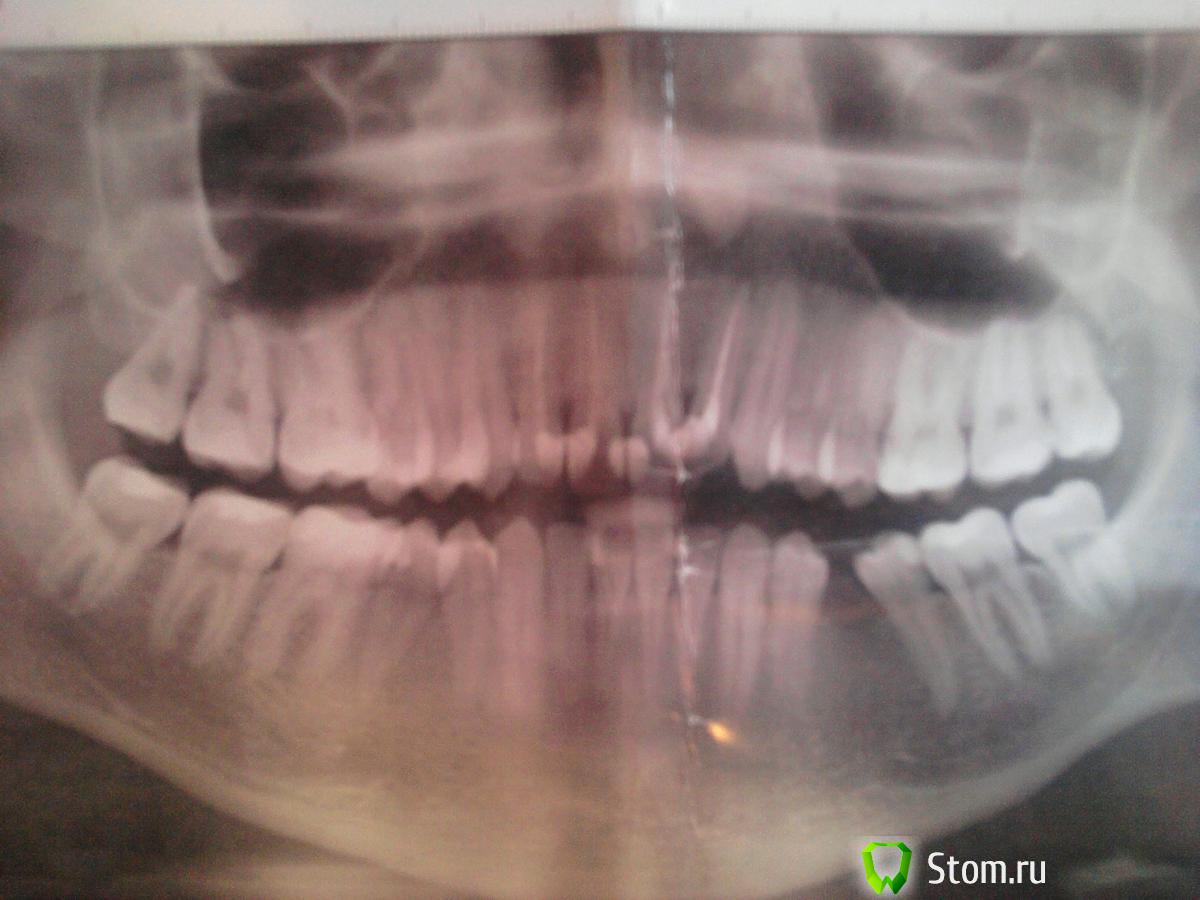

Rain Опубликовано 20 марта, 2012 Поделиться Опубликовано 20 марта, 2012 возраст 23 еще в школе было произведено удаление 36 11, 12, 21, 22 - депульпированы (периодонтит без развития пульпита из-за некачественного оказания помощи в детстве), в связи с чем врач посоветовал пока их не лечить во избежание отлома коронковой части, но там рецидивные пломбы, как поступить? кроме того 22 отклонен в вестибулярном направлении возможности обхода протезирования или имплантации имеются? какую брекет-систему предпочтительнее ставить? заранее спасибо Ссылка на комментарий

Force Опубликовано 4 апреля, 2012 Поделиться Опубликовано 4 апреля, 2012 ЗдравствуйтеНеважно, какие брекеты вы ставите, важно, какой план лечения и какие цели вы преследуете.Проблема комплексная. Это однозначно брекеты. С удалением восьмерок и раскрытием места для имплантации. Ссылка на комментарий

Force Опубликовано 5 апреля, 2012 Поделиться Опубликовано 5 апреля, 2012 Без выхлопной трубы чем машина не машина? )Для правильной организации окклюзии (прикуса) оптимально раскрыть место для имплантации отсутствующего зуба, поскольку расстояние между корнями приличное. Ссылка на комментарий

Rain Опубликовано 12 апреля, 2012 Автор Поделиться Опубликовано 12 апреля, 2012 3 ортодонта меня смотрело, сказали что оно мне не надо)) что зубы могут передние сломаться, у 35 может быть отлом корня, т.к повернут, в общем я окончательно запутался( Ссылка на комментарий